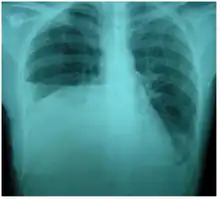

Right sided pleural effusion caused by urinothorax

Urinothorax (pl. urinothoraces) is defined as urine in the fluid-filled cavity that surrounds the lungs.[1] It is usually caused by obstructive uropathy. It is mainly diagnosed by analyzing the pleural fluid. Treatment involves treating the underlying condition, which typically results in resolution of the urinothorax. It is an extremely rare cause of pleural effusion.[2]